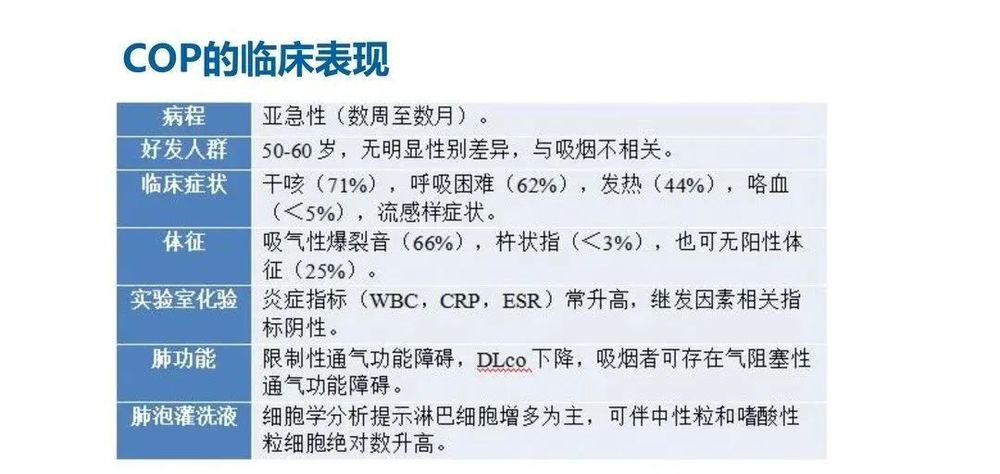

COP属于特发性间质性肺炎的一种,临床和放射学上与继发性机化性肺炎没有明显差别,但其病因目前尚不明确。COP发病率较低,男女相当,发病年龄可见于20~80岁,平均50~60岁。COP发病与吸烟无关,大多数患者不吸烟。

COP患者临床表现差异大,多数亚急性起病,发病早期常有发热、咳嗽、全身乏力等流感样症状,伴食欲减退和体质量下降,咯血、胸痛、夜间盗汗、关节痛及气胸较少见。多数患者表现为渐进性轻度呼吸困难,快速进展患者可见严重呼吸困难。大部分患者在双肺中下部可闻及吸气末Velcro啰音,部分患者可无肺部阳性体征。

实验室检查缺乏特异性,肺泡灌洗液(BALF)中细胞成分的变化对COP的诊断有一定的预测价值。除了BALF外,其他实验室辅助检查对COP的诊断帮助不大。由于临床表现缺乏特异性,COP诊断常常被延误。

COP最具特征性的表现是对抗生素无效,对激素治疗反应良好。

流行病学

COP确切发病率和患病率尚不清楚。

年龄:患者确诊时的平均年龄为50~60岁(范围,17~95岁);儿童中很少有关于COP的报道。

性别:男性发病率略高于女性(男性发病率为52%)。

吸烟史:约54%的COP患者从未吸烟,46%既往或当前吸烟;在既往或当前吸烟者中,确诊时有不到15%的人自诉当前吸烟。